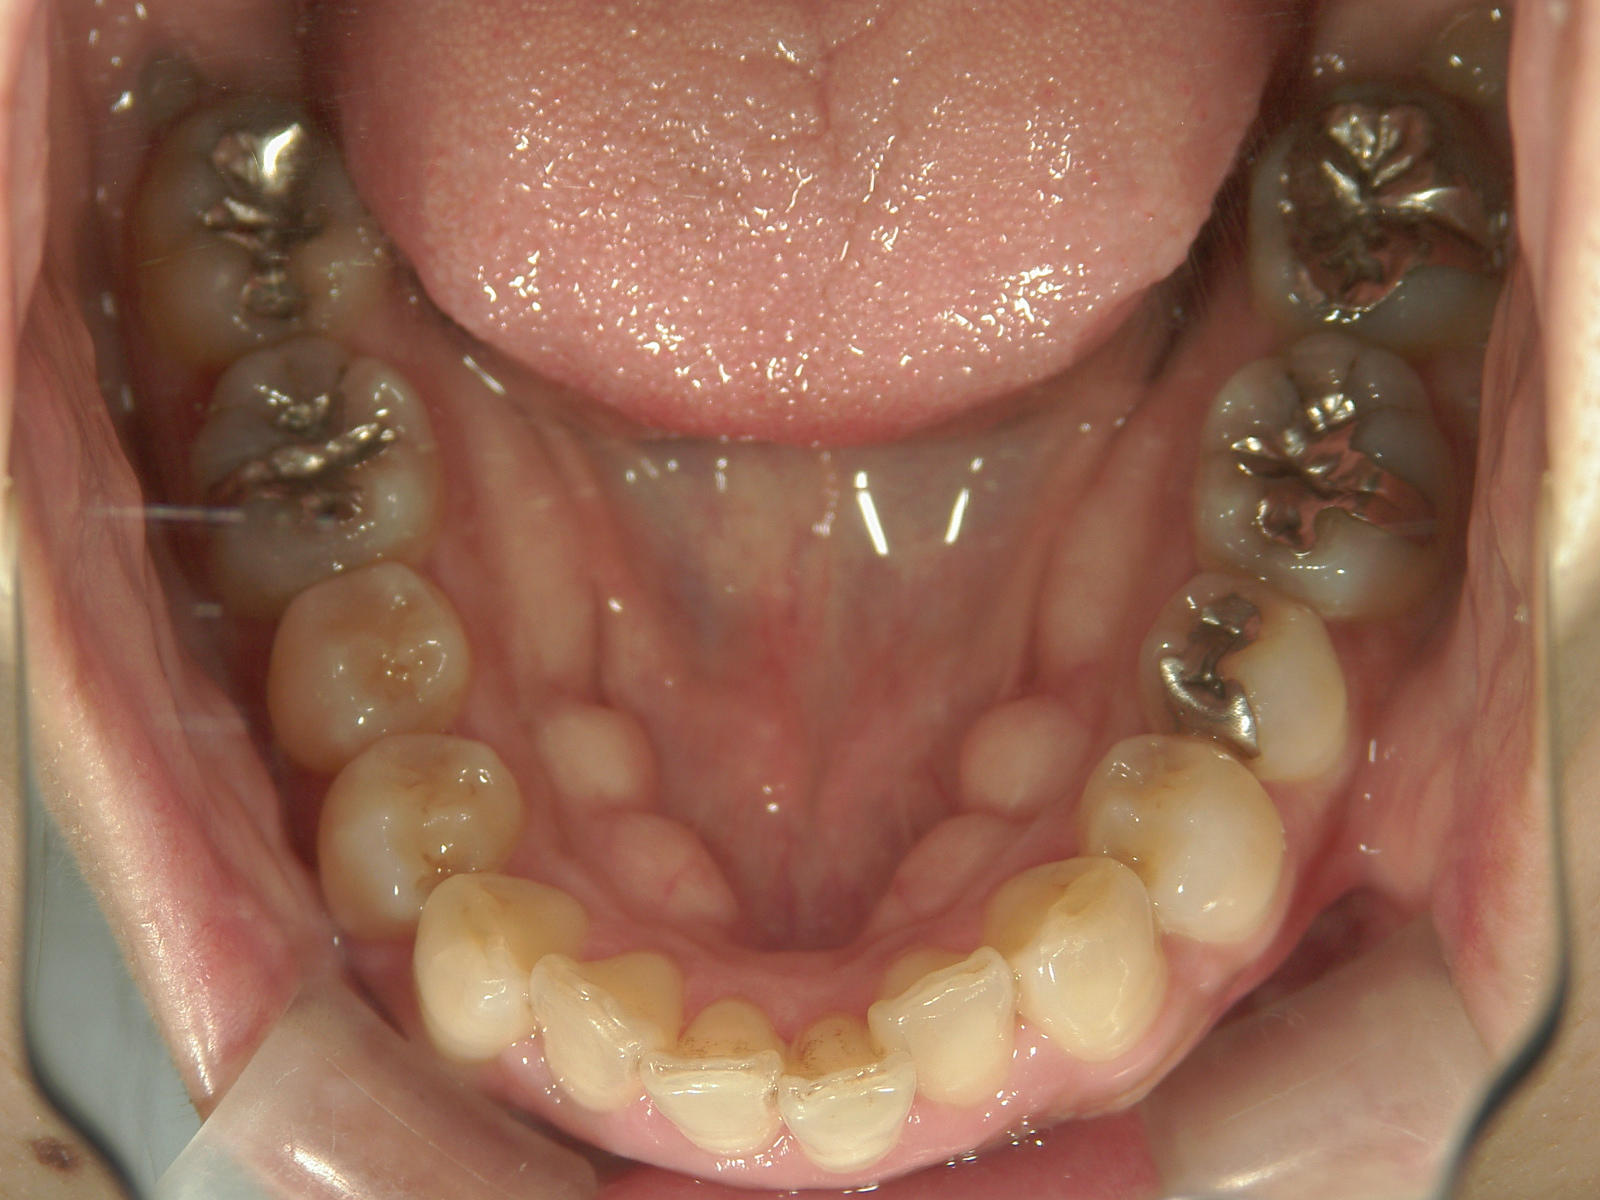

左右下 第一小臼歯2本、左上 第一大臼歯1本、右上 前歯1本を抜歯。

・抜歯した右上前歯の隣りの歯を抜歯してあいたスペースで移動。

・右上犬歯を移動して、開いたスペースへ移動。

・右上 第一小臼歯を移動して犬歯のスペースへ移動。